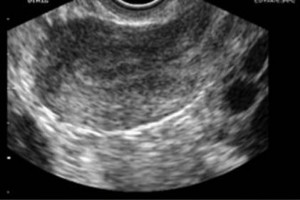

Diplomados en Ultrasonografía